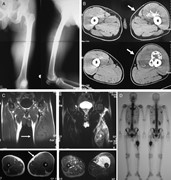

Anterior knee pain: an unusual presentation of renal cell carcinoma

John Broomfield and others

Journal of Surgical Case Reports, Volume 2014, Issue 3, March 2014, rju018, https://doi.org/10.1093/jscr/rju018